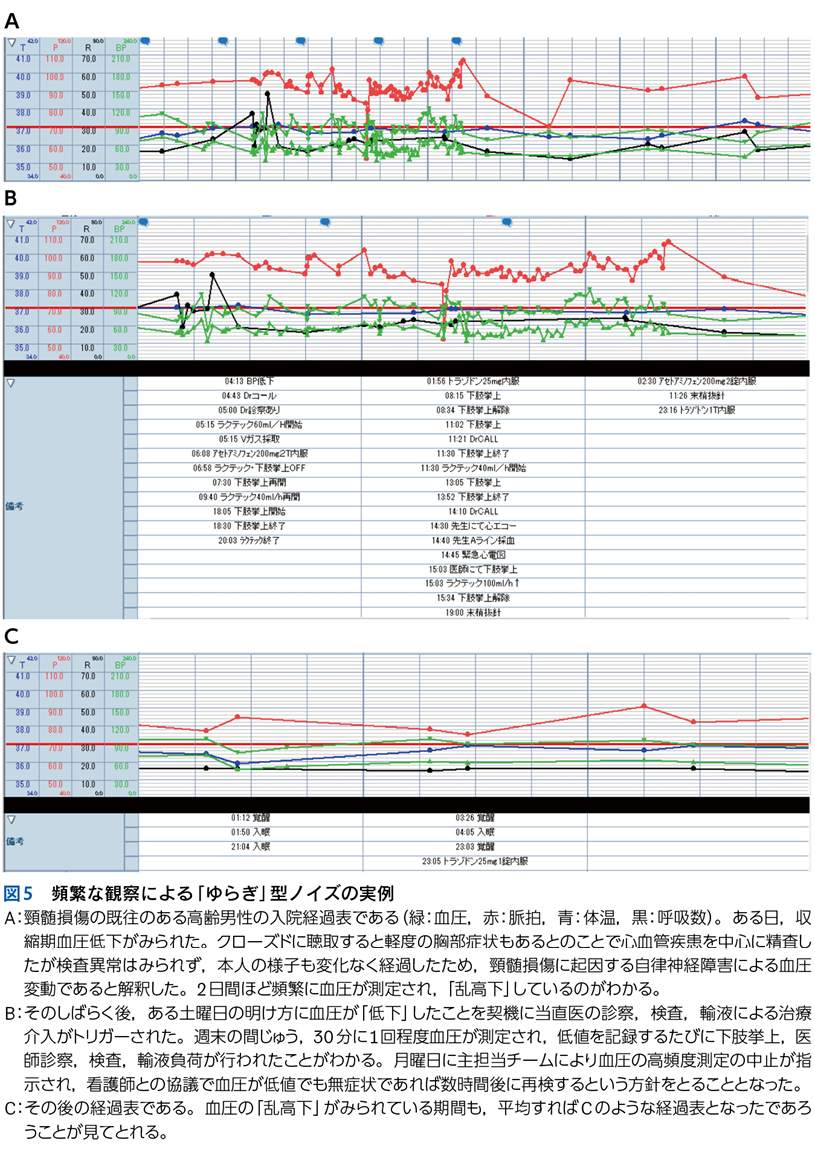

5 ノイズと多元論

▶ 「ノイズ」は,筆者的には臨床推論においてきわめて重要な概念であるため,第4章で詳述するが,フレーミングに関わるのでここで簡単に紹介しよう。ここでは「ノイズ」を,「患者の持つ情報のうち診断と直接的には関連しないもの」を指す語として使用する。対義語(診断と関連する情報)は「シグナル」である。星座のたとえで言えば「シグナル」は星座を構成する星,「ノイズ」は星座を構成しないが近傍にある「くず星」を指す(図4)。

▶ くず星とひとまとめに呼んでしまったが,厳密に言えばノイズには質的に「偽陽性情報」と「多元論で説明される情報」の2種類がある。前者は器質的疾患のシグナルではない情報であり,診断と無関係な疫学的情報,器質因のない症状,検査データのランダムなゆらぎといった,純粋に「ジャンク」な情報である。後者は併存する他疾患や合併症に起因して発せられる情報である。後者は目的としている疾患の診断という点ではノイズだが,それ自体は別の疾患により説明が可能(別疾患のシグナル)であるため,対処不要というわけではない。このような相違はあるものの,どちらもその情報を含めた一元論で状況を解釈しようとすると診断を誤るため,本書ではまとめて「ノイズ」と呼ぶ。

▶ 学会における症例報告や医学雑誌に掲載されるケースレポートは,診断が判明した後(何がノイズで何がシグナルだったか判明した後)に作成されるため,ノイズは削除され,シグナルだけが提示されることが多い。聴衆や読者は提示される情報のすべてが診断に関与する(「意味のある」情報である)ことを期待し思考できる。しかし実際の患者は“ノイズまみれ”であり,臨床現場ではノイズとシグナルを前向きに見わける努力をしながら進まなければならない。

▶ ノイズの問題点は,当然のことだが診断を誤った方向に導くことにある。ノイズ情報を含めてフレーミングを行えば(すなわち,ノイズ情報も一元的に説明できるような疾患を探すことにすれば),ノイズの定義からしてフレーム内に真の診断が存在しなくなる。したがって,フレーミングに用いる問題定義からは,ノイズを慎重に排除する必要がある。

▶ ノイズとシグナルを診断前に完全に見わけることは不可能なので,安全なのは一元論(いわゆる「オッカムの剃刀」)に過度にこだわらず,「ノイズであることが否定できない(シグナルであることが確実でない)情報はフレーミングに用いない」あるいは「ノイズであることが否定できない情報を外したバージョンのフレーミングも用意する」という謙虚な態度をとることだろう。

▶ ノイズを克服するためには,ノイズとシグナルを見わける目や謙虚な推論態度を養うだけでなく,「なるべくノイズを発生させない」情報取得戦略が必要になる。これらについては第4章で詳述する。